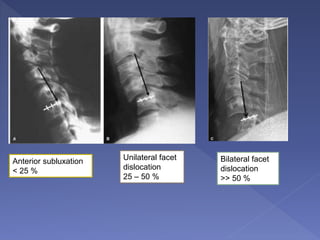

Anterior subluxation

< 25 %

Unilateral facet

dislocation

25 – 50 %

Bilateral facet

>> 50 %